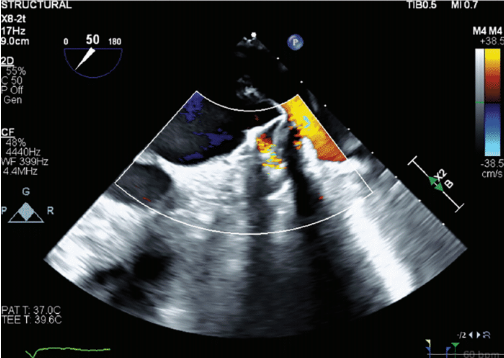

A 78-year-old woman was referred to Northside Hospital Heart Institute for possible LAAC. She had a history of coronary artery bypass grafting (CABG) over 5 years ago, permanent AF with history of atrioventricular node ablation, and permanent pacemaker implantation. Her CHA2DS2-VASc score was 5 due to hypertension, age >75, diabetes, and vascular disease. This placed her at high risk for stroke, but her cardiologist deemed her not to be a good candidate for long-term oral anticoagulation due to intracranial hemorrhage with multiple falls. An operative report of the CABG was obtained, but the report showed only 3-vessel bypass with no report of LAA ligation. Computed tomography (CT) with contrast of the heart was also obtained, which is standard practice for many of our LAAC procedures, especially for patients who have had prior cardiac surgeries. There was a 5.3-mm leak noted at the surgical closure at the base of the LAA (Figure 1). This leak was too large to close with endovascular coils, and there was concern about using an endovascular plug due to length of the leak and possible effects of radial forces over time in the channel. The Amplatzer Amulet device was chosen for this case, with the plan to place the lobe inside the LAA and place the disc covering the channel with forces after closure to be axial in direction. The procedure was performed under general anesthesia and transesophageal echocardiography (TEE) imaging. LAAC procedures at Northside Hospital Heart Institute are usually performed using TEE guidance only, with no use of contrast, since our noninvasive physicians (Drs John Ricketts and Colin O’Brian) provide imaging for transseptal puncture, device deployment, and post-imaging for any leaks, including 3D TEE at every step when needed. Due to the unusual nature of this anatomy, we performed contrast fluoroscopy of the LAA. Figures 2A and 2B show the pre-implant and periprocedural TEE images. Figure 3 shows the contrast injection through the 12 French Torque Vue 45-degree Amulet delivery sheath (Abbott) and the Glidewire (Terumo Interventional Systems) in the LAA. The placement was primarily guided by TEE imaging. The smallest size (16 mm) Amulet device was chosen for closure. Figure 4 demonstrates placement under fluoroscopy. Figures 5A and 5B demonstrate closure using TEE imaging. Post procedure, the patient was placed on aspirin and clopidogrel for 3 months. Once adequate seal is confirmed at 3 months, the goal is for the patient to switch to aspirin (81 mg).